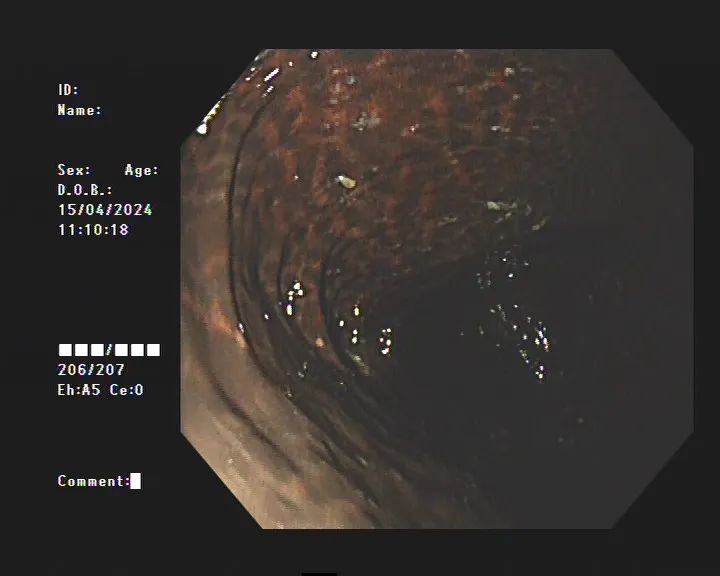

此时,整个肠道变黑,布满斑点。

就像豹纹一样

如果查不清楚,查了一下就震惊了!患者整个大肠内壁呈棕黑色蛇皮状变化,黑色素沉积明显,诊断为“结肠黑变病”。如果继续发展,可能会发生癌变。

据专家介绍,临床上很多患者口服药物后,对结肠镜检查有不同程度的结肠黑变病。正常的结肠粘膜和我们的口腔粘膜一样,是淡红色的,看起来光滑光滑,粘膜表面的小血管线条清晰可见。但结肠黑变病的肠粘膜呈棕褐色,有豹纹或蛇皮状条纹,甚至严重变黑。

结肠性黑变病患者